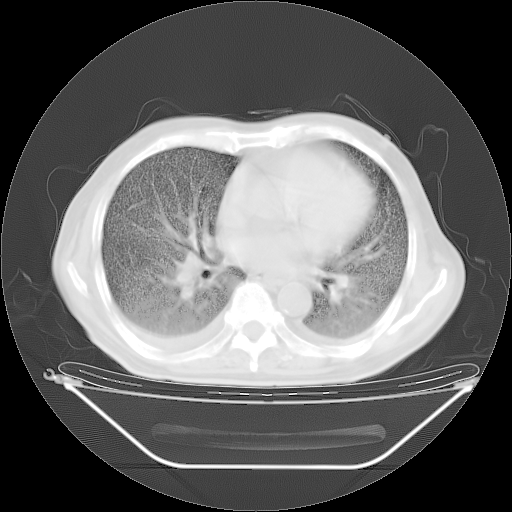

今天复查肺部CT,发现双肺广泛磨玻璃样改变。所以我把3月19日和5月9日相隔50天的肺部CT上传。请大家会诊。

2009年3月19日肺部CT片。

2009年3月19日肺部CT